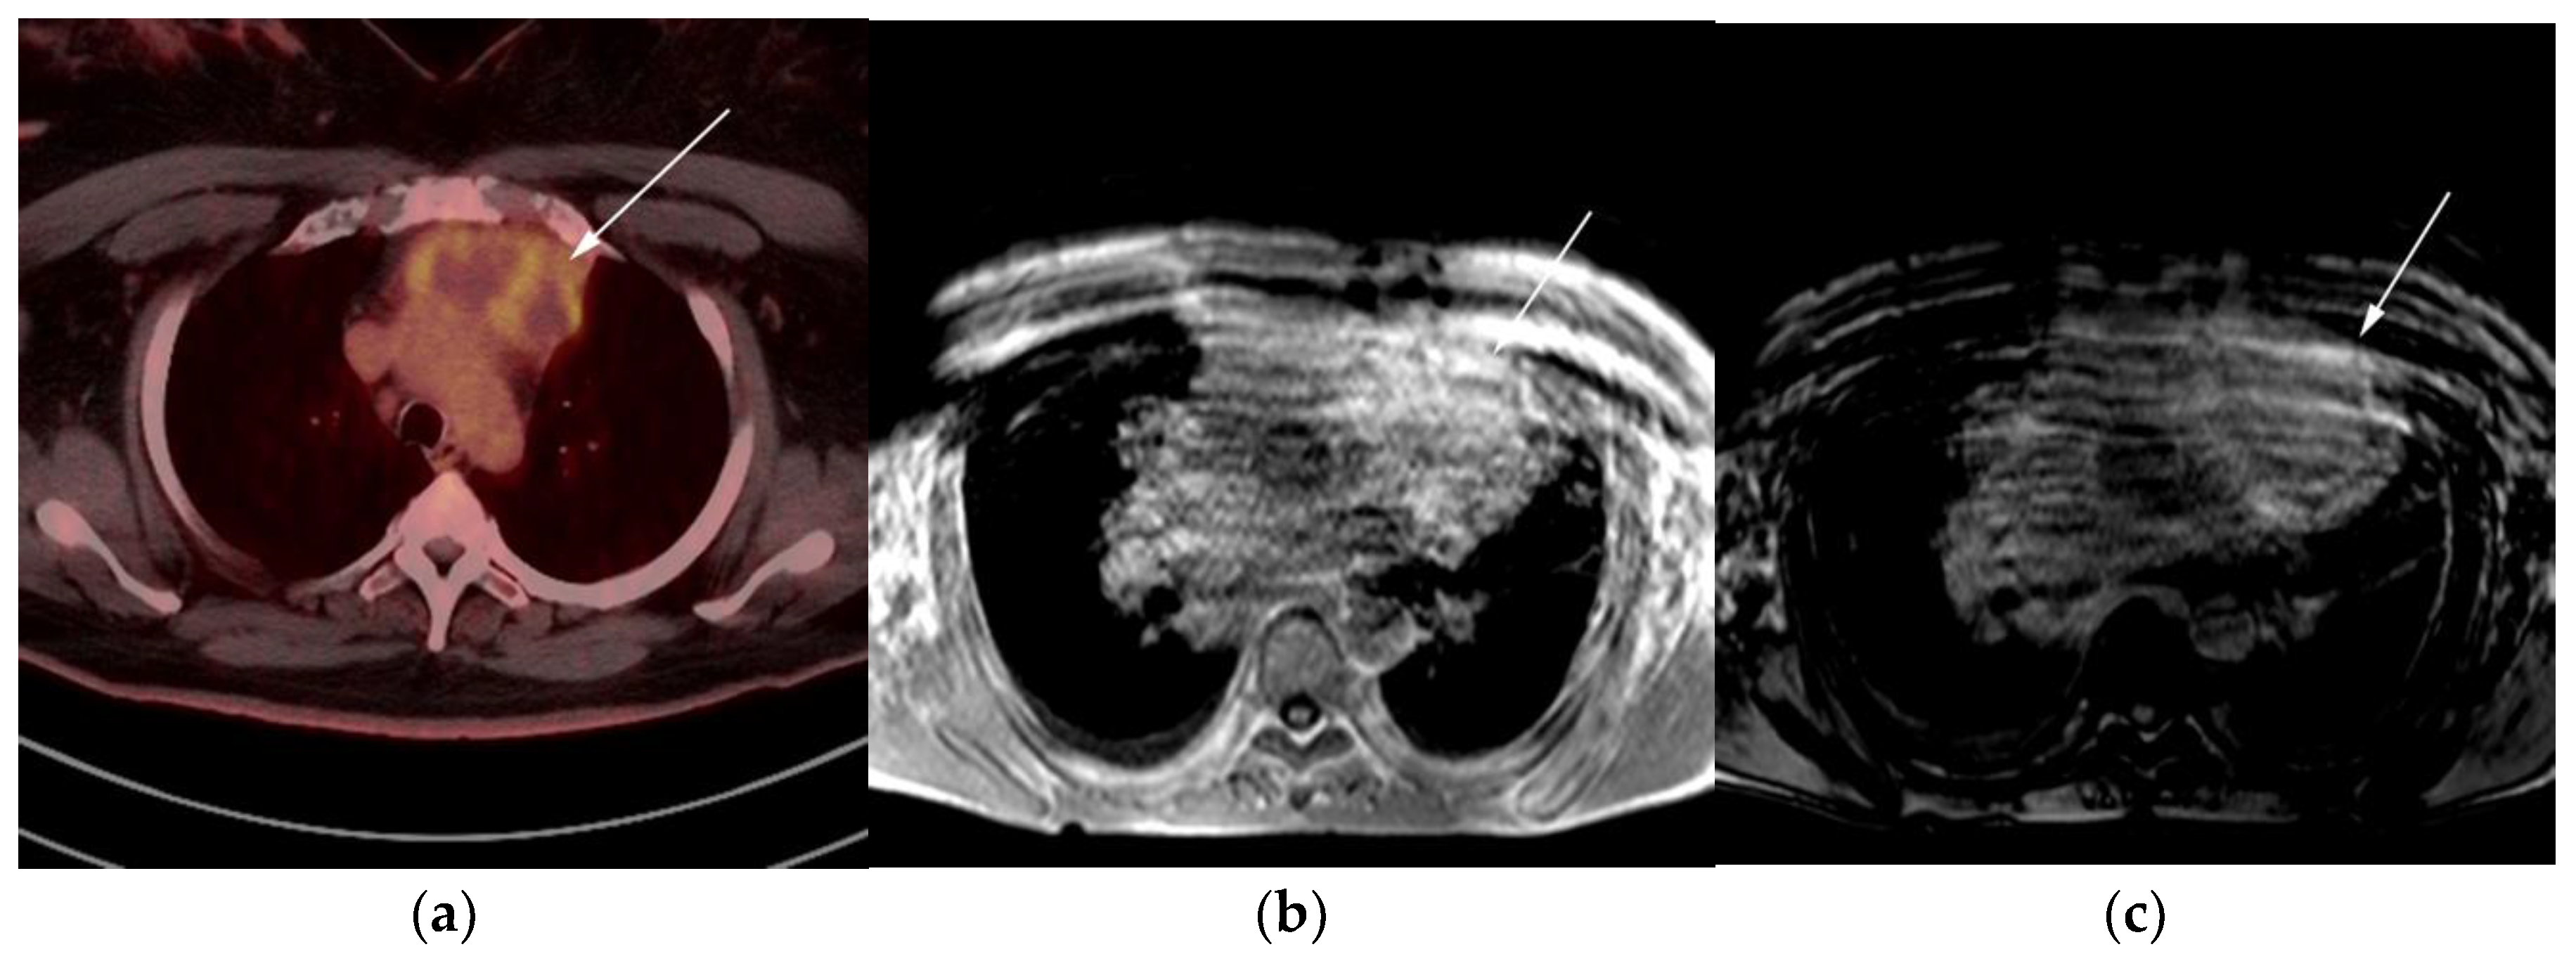

Figure 5.

A 24-year-old female presenting with cough and dyspnea with plethora of the face. (a) Maximal intensity projection (MIP) FDG PET/CT shows hypermetabolic anterior mediastinal mass (white arrows) with no other sites of disease involvement in the body. (b) Coronal contrast-enhanced CT image shows significant vascular and airway compromise by an ill-defined anterior mediastinal mass (white arrow). Biopsy-proven primary mediastinal B-cell lymphoma. Main differential diagnosis would be Hodgkin’s lymphoma. However, unlike in Hodgkin’s lymphoma, primary mediastinal B-cell lymphoma often shows frequent invasion of the mediastinal vessels, frequently resulting in superior vena cava syndrome.

The use of 18F-FDG PET/CT is essential in the evaluation of patients with PMLBCL to reveal sites of disease not visible on CT and to provide more accurate staging and radiation field planning (Figure 6). 18F-FDG PET/CT may also be beneficial for restaging after chemotherapy and/or radiotherapy, or when relapse is suspected [34]. Negative 18F-FDG PET/CT after two or four cycles of chemotherapy has a negative predictive value and may predict excellent outcome in patients, achieving complete response without relapse. Patients who have residual activity equal to or higher than liver activity after immunochemotherapy treatment are more likely to relapse. In such instances, the addition of radiotherapy to the treatment regimen should be considered to avoid relapse in those high-risk patients. Relapse usually occurs within 1 year and is more likely to be widespread, involving distant extranodal sites such as the CNS, liver, kidneys, adrenal glands, GI tract, ovaries, and pancreas. Late relapses are very uncommon [35]. 18F-FDG PET/CT can also efficiently assess post-treatment response, differentiating between necrotic or fibrotic tissue and residual masses containing viable tumor [33,36]. There are various potential challenges to 18F-FDG PET/CT post-treatment implementation, including false-positive results secondary to thymic rebound hyperplasia, specifically seen in the young population. This can be limited by increasing the interval between treatment and imaging. Additionally, MRI can be helpful in those cases, and high signal on T1 in phase imaging with loss of signal on the out of phase sequences is consistent with thymic rebound hyperplasia (Figure 7 and Figure 8) [34,37].

Figure 6.

Imaging in a different patient with known diagnosis of primary mediastinal B-cell lymphoma. (a) Axial FDG PET/CT images show the hypermetabolic anterior mediastinal mass (white arrows), and there is also central areas of absent metabolic activity within the mass (red arrow), correlating with areas of fibrosis, a finding that is essential in prebiopsy planning to avoid false negative results. (b) Axial FDG PET/CT images show hypermetabolic right upper paratracheal nodes (white arrows) and several additional hypermetabolic pulmonary and pleural-based nodules within right upper lung (red arrows). (c) H&E section shows that the tumor is composed of large, atypical cells with reniform or multi-lobulated nuclei with abundant clear cytoplasm. Note the lymphoma cells are compartmentalized by the prominent sclerotic bands of fibrosis. (Original magnification 400x, H&E stain).